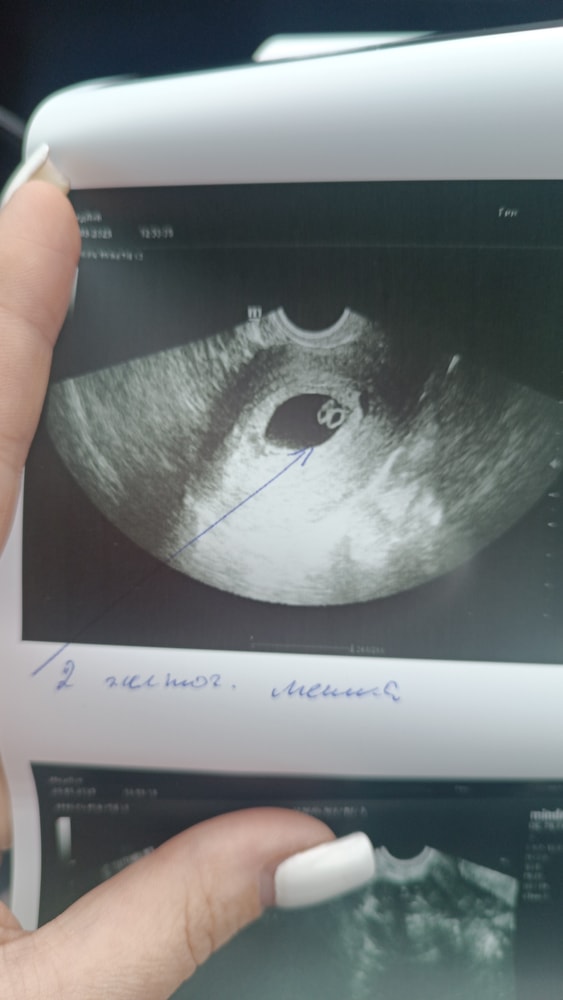

УЗИ в 7 недель и 5 дней

В смысле какова вероятность? 2 сердца же,вероятность 100% или я чего не догоняю

Катерина, тоже видите что 100% двое?)

Анна Семёнова, думаю да)

У вас практически 100% )))

Оксана, у меня не то что шок, у меня гипершок) это реально прям близнецы?)

Анна Семёнова, реально) самые настоящие!)))) те которые похожи друг на друга сильно)